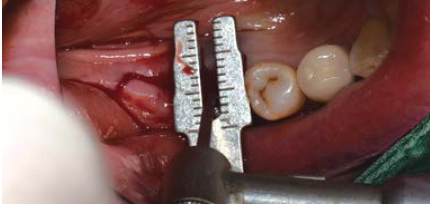

Volume Up Gauge로 직경 확인 (Ø8.5)

-

Volume Up Gauge홈에 맞춰 Point Drill 위치

Point Drill 후 생성된 구멍에 Ø8.5 Volume Up Parallel Pin을 끼움

이 후, 앞의 임플란트 위치에 맞춰 Volume Up Gauge 위치 시켜 직경확인 (Ø7.5)

Volume Up Gauge 홈에 맞춰 Point Drill 위치

Point Drill 후 생성된 구멍에 Ø7.5 Volume Up Parallel Pin을 끼움